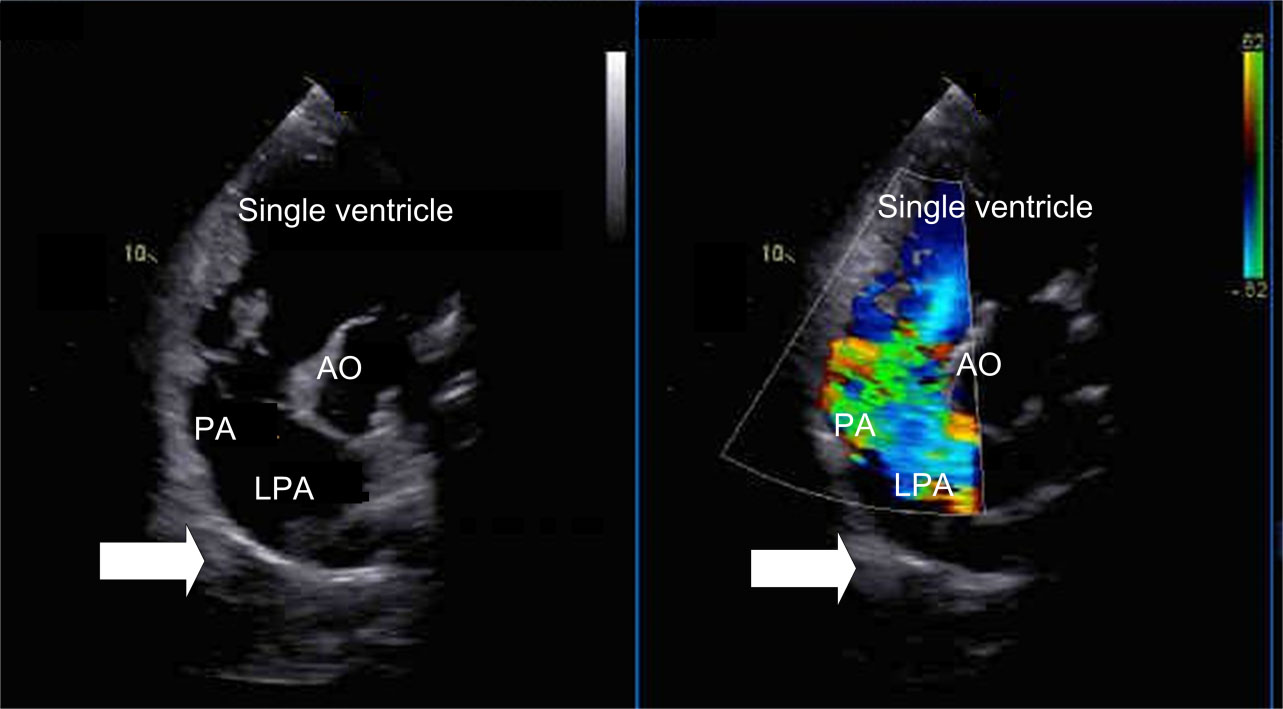

The absence of right pulmonary artery combined with single ventricle and endocardial cushion defect. There is no right pulmonary artery structure in the trunk of pulmonary artery as shown in Figs. 2,3 (hypertension group). The regurgitation peak velocity (Vmax) was 411 cm/s and pressure gradiant (PGmax) was 67 mmHg (means the mean pulmonary arterial pressure is estimated to be 67 mmHg). There is no normal ventricular septal structure in the ventricular cavity. The left and right atrium communicated with the common ventricle through the common atrioventricular valve; Combined with partial endocardial cushion defect: the normal crisscross structure between atrioventricular septum and atrioventricular valve disappear, and the echo below the atrial septum is lost.

Fig. 2.Right pulmonary artery absence with single ventricle. (a) Suprasternal long axis view (2D image). In this view there is not right pulmonary artery structure from the main pulmonary artery (arrow). LPA, left pulmonary artery. (b) High level parasternal view (2D image). In this view there is only left pulmonary artery structure from the main pulmonary artery (arrow). LPA, left pulmonary artery; MPA, Main pulmonary artery.

Fig. 3.Non-standard four-chamber section (Color Doppler and 2D image). In this view there is not right pulmonary artery structure from the main pulmonary artery (arrow). PA, main pulmonary artery; LPA, left pulmonary artery; AO, Aorta.